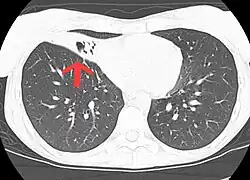

CT scan of patient with right middle lobe aspiration and Mycobacterium avium infection.

MAC usually affects patients with abnormal lungs or bronchi. However, Jerome Reich and Richard Johnson describe a series of six patients with MAC infection of the right middle lobe or lingula who did not have any predisposing lung disorders.[17][18]

The right middle lobe and lingula of the lungs are served by bronchi that are oriented downward when a person is in the upright position. As a result, these areas of the lung may be more dependent upon vigorous voluntary expectoration (cough) for clearance of bacteria and secretions.